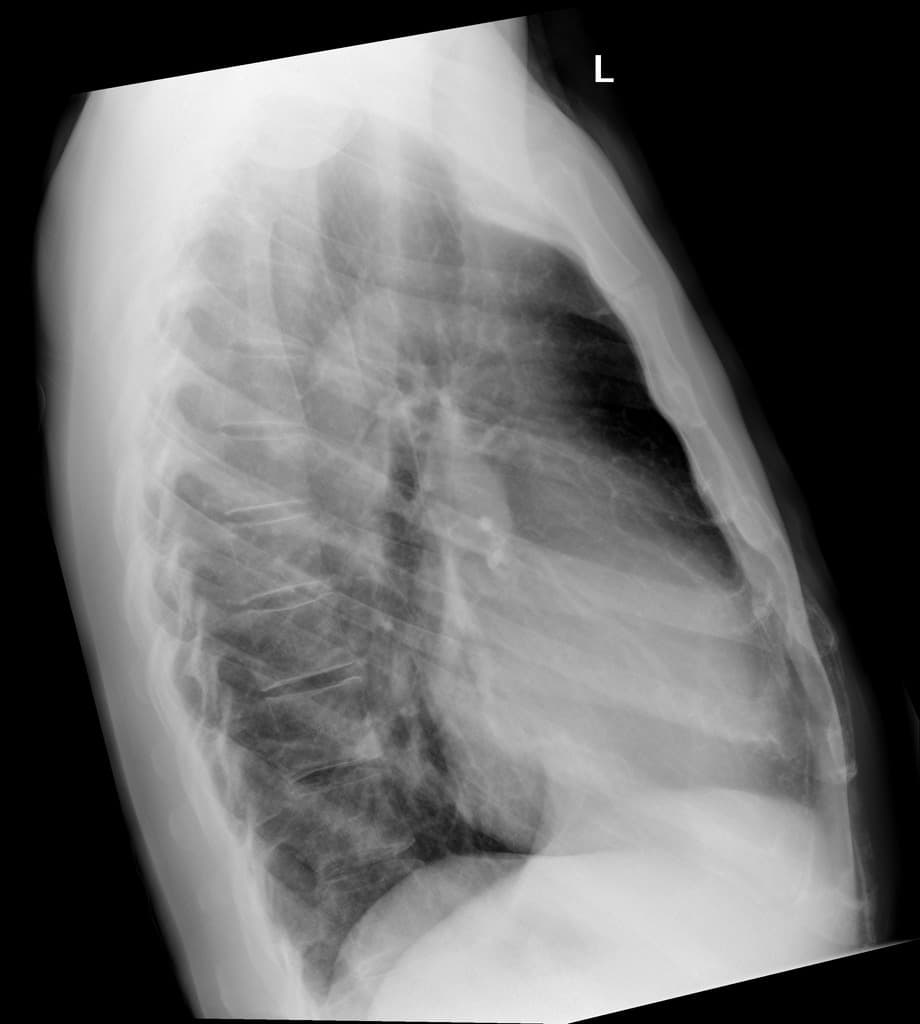

- Hơn 20 nốt nhỏ ở mỗi phổi, kích thước tối đa 6 mm, nhiều nốt có vùng mờ kính (ground-glass attenuation) xung quanh, gợi ý bệnh lý di căn xuất huyết (hemorrhagic metastatic disease).

- Tràn dịch màng phổi (pleural effusion) hai bên, lượng ít.

- "Các nốt phổi kèm vùng mờ kính xung quanh gợi ý di căn xuất huyết, đặc trưng của u ác tính mạch máu."